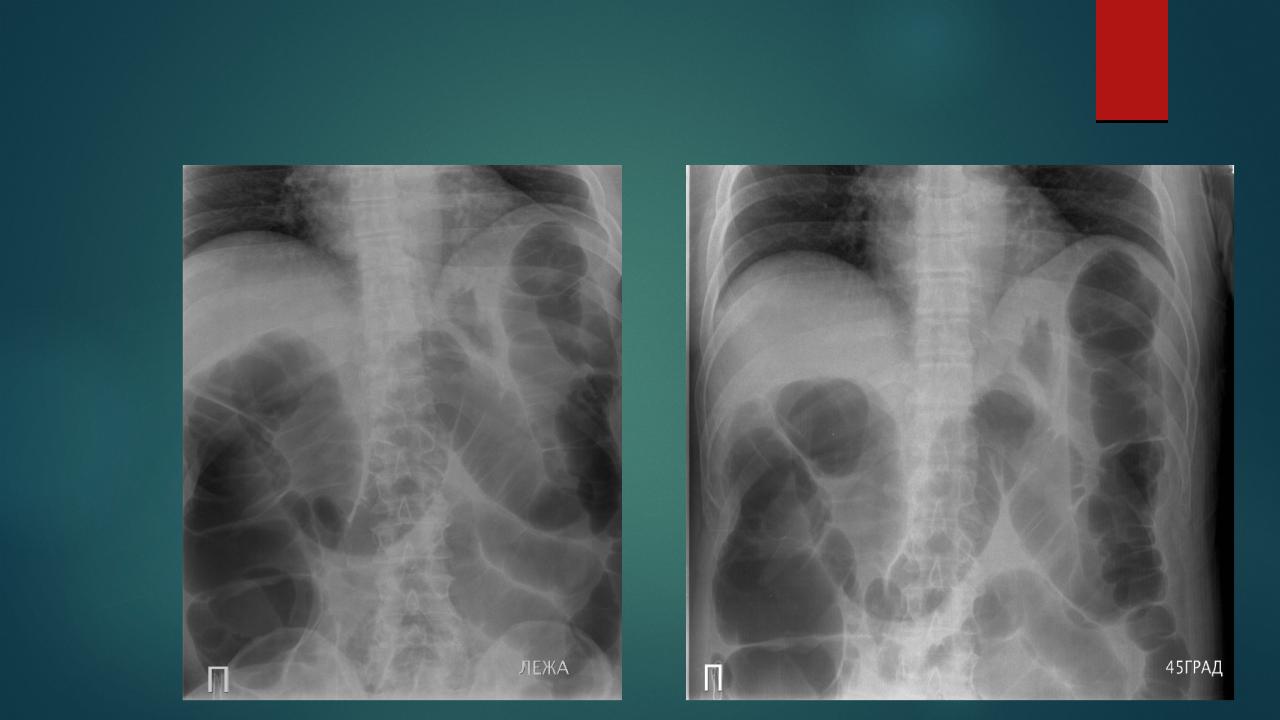

Нормы обзорной рентгенографии брюшной полости